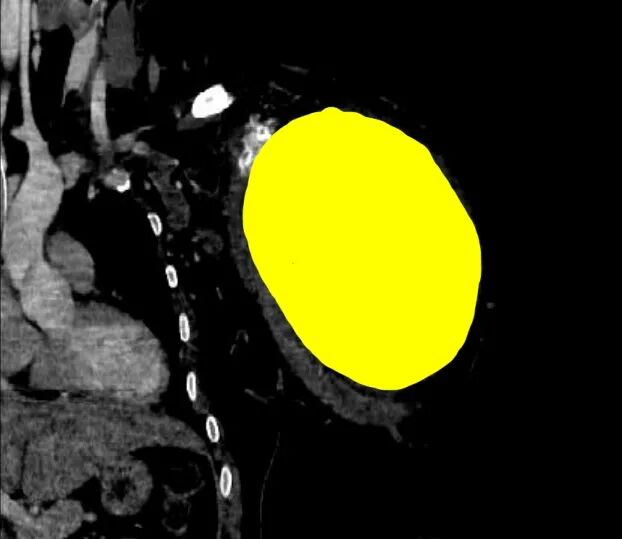

↑CT扫描中,识别出1个病灶(骨肿瘤)

CT三维重建后处理是CT检查的延伸,是计算机技术在影像医学中的具体应用形式,这种技术可以对患者扫描的信息进行处理和重建,将信息转化为三维立体的图像,能够更加清晰地观察到患者病变部位的具体情况,让骨肿瘤位置、大小、浸润情况等清晰可见,从而提高骨肿瘤诊断准确率。为临床诊断和后续治疗提供可靠的参考依据,提高预后,值得临床推广和借鉴[2]。